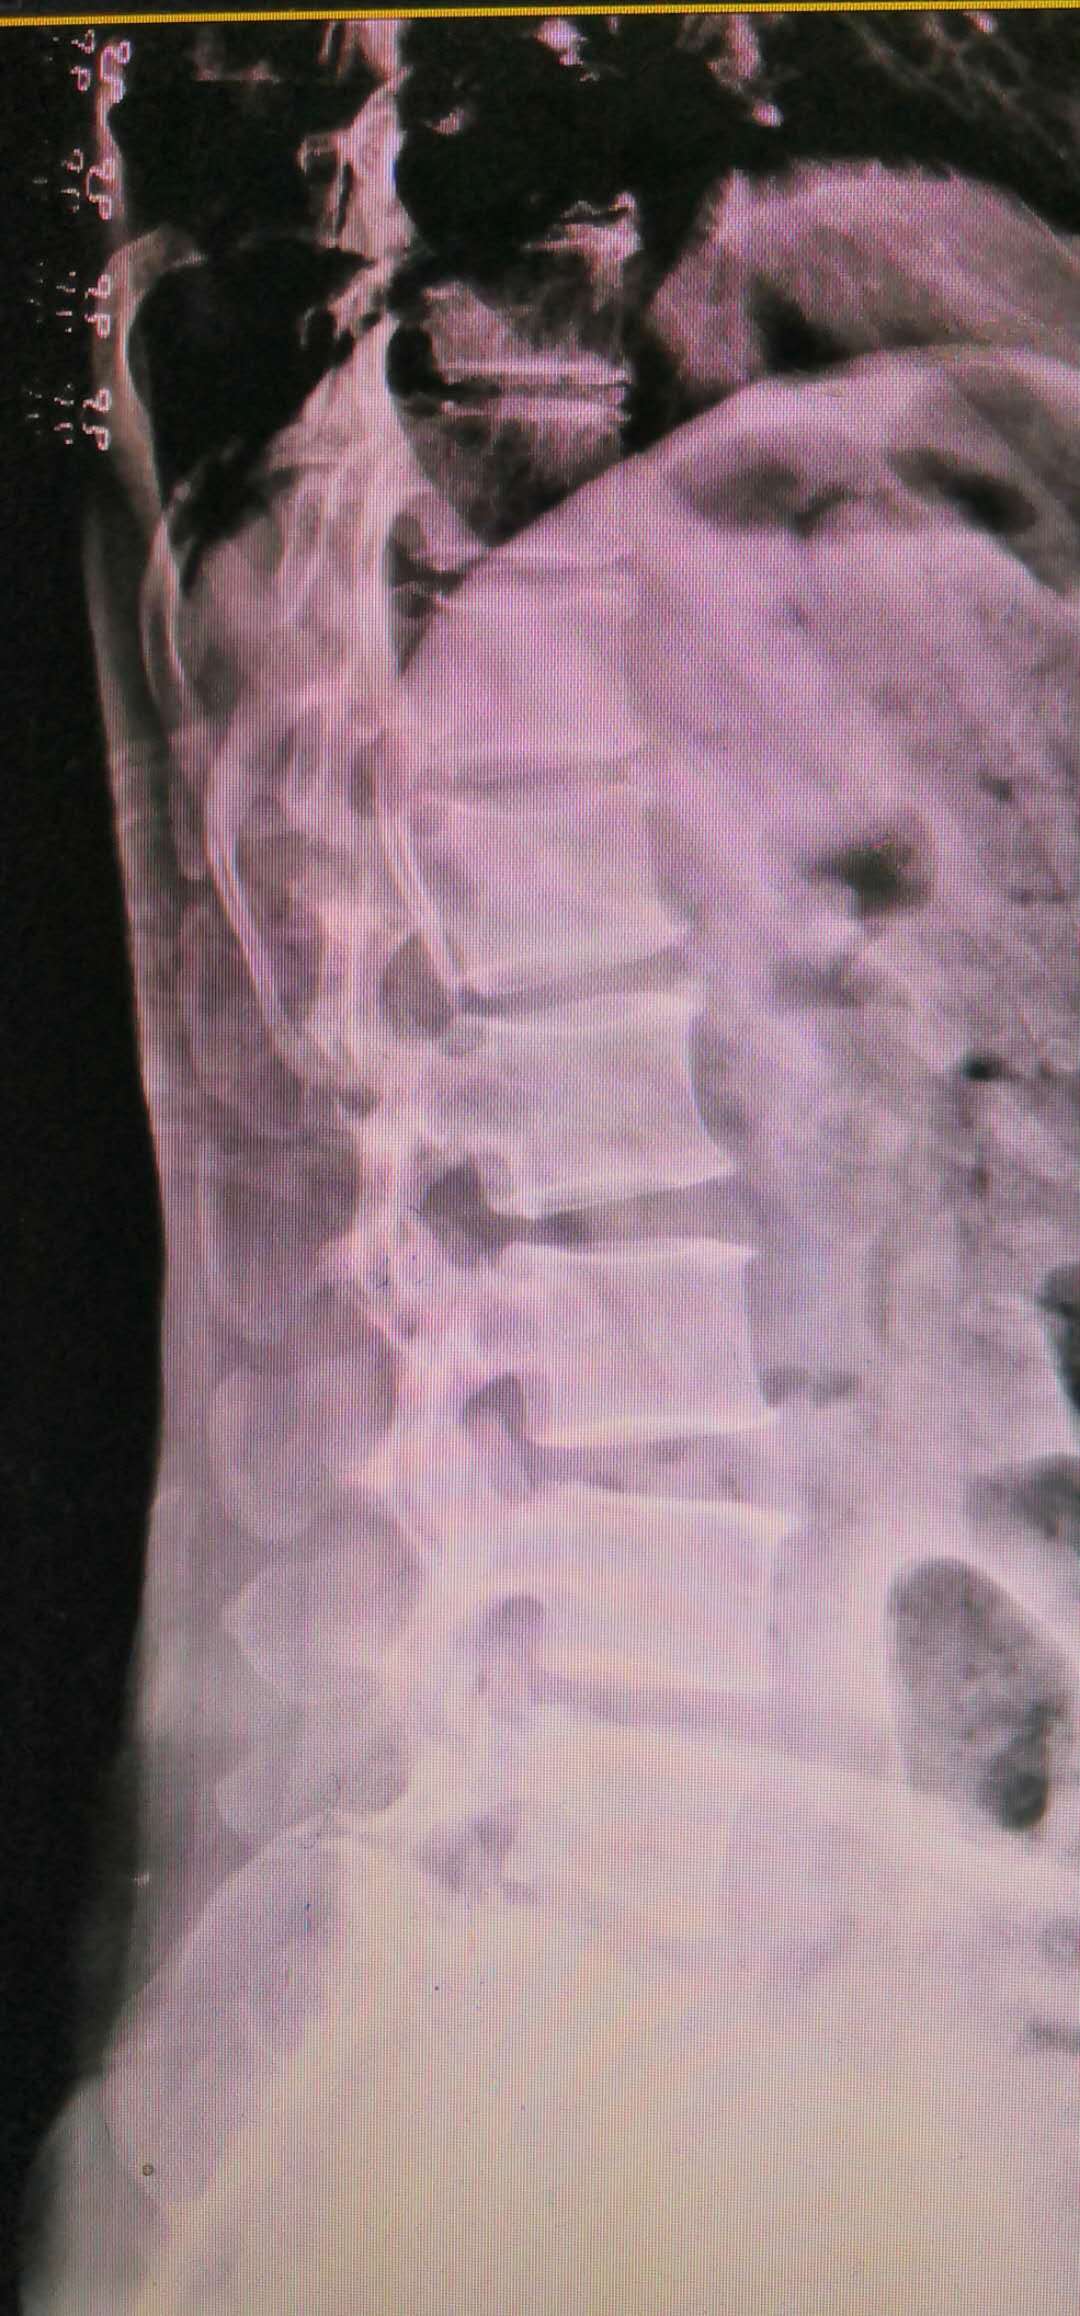

而腰椎不稳的图片完全不一样,如下图所示:

脊柱侧弯,L4椎体前度滑脱